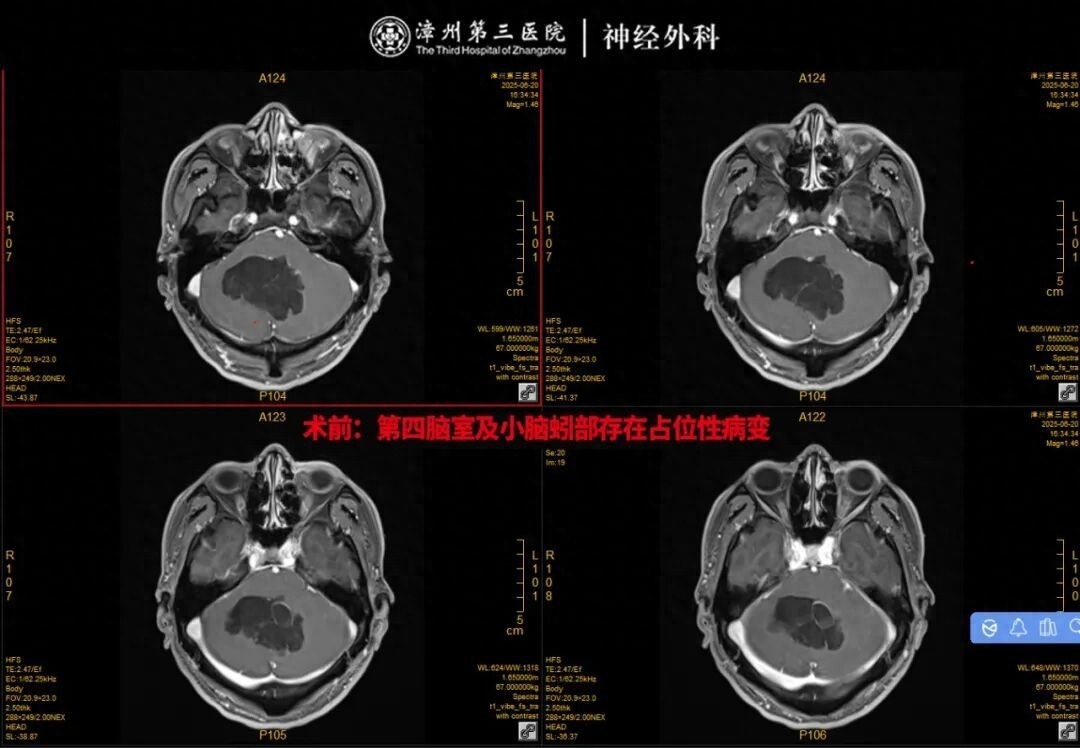

神经外科医师蚁集张先生的症状,第一期间安排了颅脑磁共振(MR)查验。查验收尾显露他的第四脑室及小脑蚓部存在占位性病变,且有恶性的可能性;同期,幕上脑室出现彭胀,还伴有间质性脑水肿。

“这个位置太特殊了!”神经外科团队诠释谈,第四脑室和小脑蚓部紧邻脑干,脑干是东谈主体的“性射核心”,崇拜阻抑呼吸、心跳、意志等核心功能,稍有毁伤就可能导致严重效果,甚而危及生命。更毒手的是,该区域空间褊狭,神经血管密集,手术操作的容错率极低,不仅需要精委果除病变,还要最大法例保护周围正常组织,手术难度和风险齐荒谬高。

为了确保手术万无一失,由林友城副院长组织多学科众人进行详备的术前扣问,团队反复策划张先生的影像膏火力,一一瞥查可能出现的风险点,最终制定了一套周到驻扎的手术决议,行“显微镜下等四脑室占位切除术+颅骨整复术”。